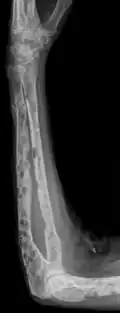

-

X-ray of the forearm, with lytic lesions -

Multiple myeloma in the upper arm -

Humerus with multiple myeloma lesions -

Same humerus before, with just subtle lesions